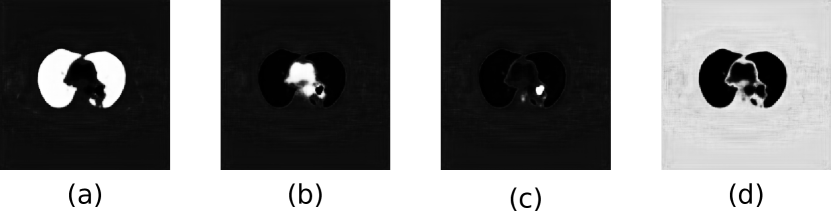

After the last reconstruction block, the output feature map has the same width and height as the input PET-CT image, with 64 channels in the third dimension. This is analogous to a final 64-dimensional feature vector for each pixel in the original image. We then use a 11 convolution to map these feature vectors into feature maps, where is the number of ROIs. This obtains for each pixel a vector corresponding to the observed activations for each ROI class as well as an ‘other’ class comprising all other image contents. We use the term ‘other’ rather than ‘background’ as this region encompasses the ‘true’ PET-CT background (areas of the image outside the field of view of the scanner that have a zero pixel value) as well as non-zero pixel areas within the image that are not of interest in the task (e.g., skin and subcutaneous fat of the chest wall, arms, etc.). Finally, we transform these observations into a probability or prediction map that corresponds to the likelihood of the pixel belonging to a particular class using the softmax function [72]:

| (5) |

where is the probability that the pixel with observation vector belongs to the region , is the -th element of vector and is the activation corresponding to region . The ‘other’ class (and hence the summation for regions in the denominator of Equation 5) is necessary to formulate the final output of our co-learning CNN as a set of probability maps. The ‘other’ class probability map ensures the sum of probabilities for each pixel has a total of 1 by capturing the probability that a pixel does not belong to any of the ROIs. The use of an additional class to compute the probability of non-ROI regions is a standard formulation that has been used in prior CNN research [73]. Fig. 4 is an example of the probability maps generated for the classes used in our experiments (lung fields, mediastinum, tumors), and the ‘other’ class.